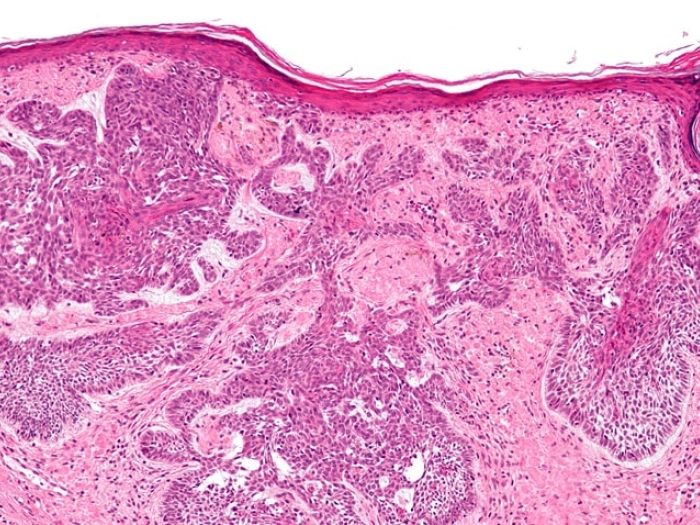

Detecting When the Most Common Skin Cancer Turns Dangerous

A University of Michigan study finds a biomarker associated with basal cell carcinoma may help signal which skin tumors will be more aggressive.